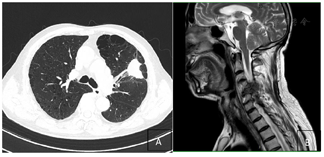

实验室检查:血细胞分析:红细胞2.93×10^12/L↓;血红蛋白103.00g/L↓;白细胞3.40×10^9/L↓;中性粒细胞绝对值1.77×10^9/L↓;肝功能:白蛋白37.50g/L↓;总蛋白58.00g/L↓;电解质(血液):钾3.44mmol/L↓;免疫功能检测提示多项指标低下。影像学检查:脑MRI、全身骨扫描、腹部彩超未见明显异常。胸部CT增强(治疗前后):2021年5月左肺上叶前段软组织密度影(4.3×2.4cm)(图1)。治疗后左肺上叶舌段肿块(大小约2.5×1.6cm),较前减小(图2)。颈椎MRI(治疗前后):2021年5月颈5椎体病理性骨折、左侧椎旁软组织肿块形成(图1)。治疗后左侧椎旁软组织肿块较前缩小(图2)。